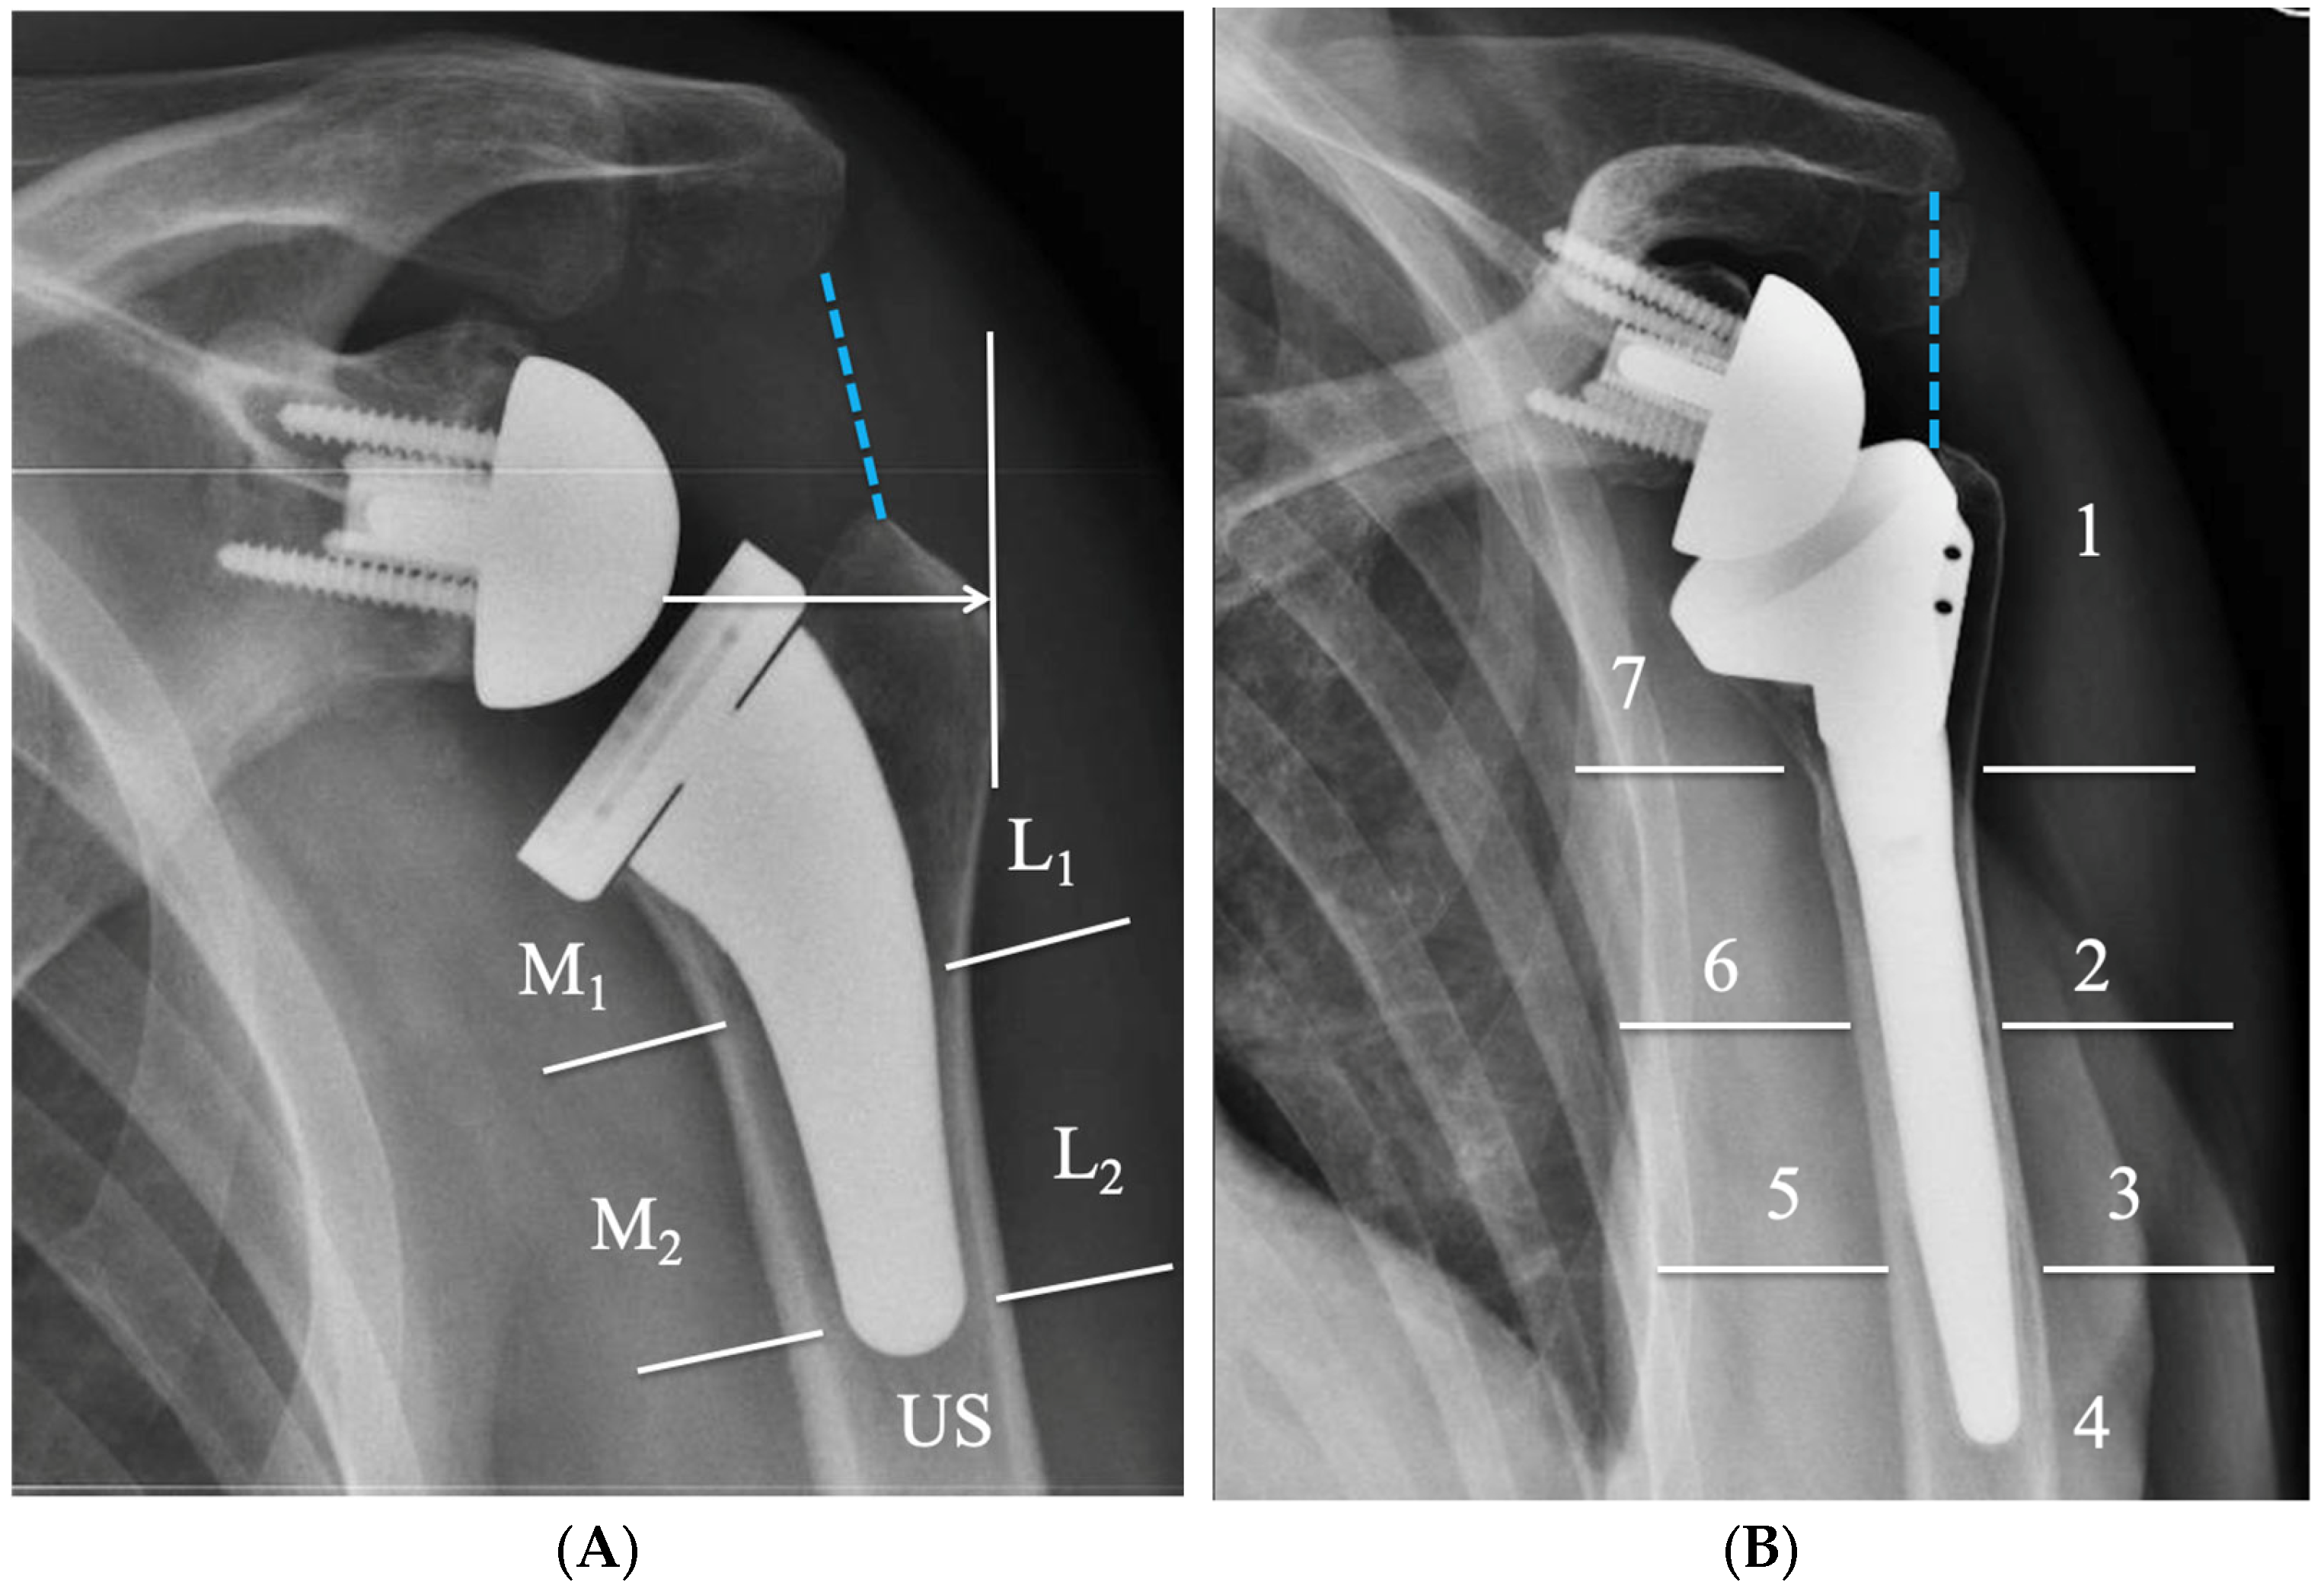

4. Radiographic Evaluation of Grammont-Style Reverse Arthroplasty

5. Radiographic Features of Lateralized Reverse Arthroplasty

- Lädermann, A.; Chiu, J.C.-H.; Cunningham, G.; Hervé, A.; Piotton, S.; Bothorel, H.; Collin, P. Do Short Stems Influence the Cervico-Diaphyseal Angle and the Medullary Filling after Reverse Shoulder Arthroplasties? Orthop. Traumatol. Surg. Res. 2020, 106, 241–246. [Google Scholar] [CrossRef] [PubMed]

- Tross, A.K.; Woolson, T.E.; Nolte, P.C.; Schnetzke, M.; Loew, M.; Millett, P.J. Primary Reverse Shoulder Replacement with a Short Stem: A Systematic Literature Review. JSES Rev. Rep. Tech. 2021, 1, 7–16. [Google Scholar] [CrossRef] [PubMed]

- Harmsen, S.M.; Norris, T.R. Radiographic Changes and Clinical Outcomes Associated with an Adjustable Diaphyseal Press-Fit Humeral Stem in Primary Reverse Shoulder Arthroplasty. J. Shoulder Elb. Surg. 2017, 26, 1589–1597. [Google Scholar] [CrossRef] [PubMed]

- Sanchez-Sotelo, J.; Wright, T.W.; O’Driscoll, S.W.; Cofield, R.H.; Rowland, C.M. Radiographic Assessment of Uncemented Humeral Components in Total Shoulder Arthroplasty. J. Arthroplast. 2001, 16, 180–187. [Google Scholar] [CrossRef]

- Sperling, J.W.; Cofield, R.H.; O’Driscoll, S.W.; Torchia, M.E.; Rowland, C.M. Radiographic Assessment of Ingrowth Total Shoulder Arthroplasty. J. Shoulder Elb. Surg. 2000, 9, 507–513. [Google Scholar] [CrossRef]

- Werner, B.S.; Jacquot, A.; Molé, D.; Walch, G. Is Radiographic Measurement of Acromiohumeral Distance on Anteroposterior View after Reverse Shoulder Arthroplasty Reliable? J. Shoulder Elb. Surg. 2016, 25, e276–e280. [Google Scholar] [CrossRef]

- Kim, D.-H.; Choi, H.-U.; Choi, B.-C.; Kim, J.-H.; Cho, C.-H. Postoperative Acromiohumeral Interval Affects Shoulder Range of Motions Following Reverse Total Shoulder Arthroplasty. Sci. Rep. 2022, 12, 21011. [Google Scholar] [CrossRef]

- Lädermann, A.; Williams, M.D.; Melis, B.; Hoffmeyer, P.; Walch, G. Objective Evaluation of Lengthening in Reverse Shoulder Arthroplasty. J. Shoulder Elb. Surg. 2009, 18, 588–595. [Google Scholar] [CrossRef] [PubMed]

- Lädermann, A.; Edwards, T.B.; Walch, G. Arm Lengthening after Reverse Shoulder Arthroplasty: A Review. Int. Orthop. 2014, 38, 991–1000. [Google Scholar] [CrossRef] [PubMed]

- Ferrier, A.; Blasco, L.; Marcoin, A.; De Boissieu, P.; Siboni, R.; Nérot, C.; Ohl, X. Geometric Modification of the Humeral Position after Total Reverse Shoulder Arthroplasty: What Is the Optimal Lowering of the Humerus? J. Shoulder Elb. Surg. 2018, 27, 2207–2213. [Google Scholar] [CrossRef]

- Boutsiadis, A.; Lenoir, H.; Denard, P.J.; Panisset, J.-C.; Brossard, P.; Delsol, P.; Guichard, F.; Barth, J. The Lateralization and Distalization Shoulder Angles Are Important Determinants of Clinical Outcomes in Reverse Shoulder Arthroplasty. J. Shoulder Elb. Surg. 2018, 27, 1226–1234. [Google Scholar] [CrossRef] [PubMed]